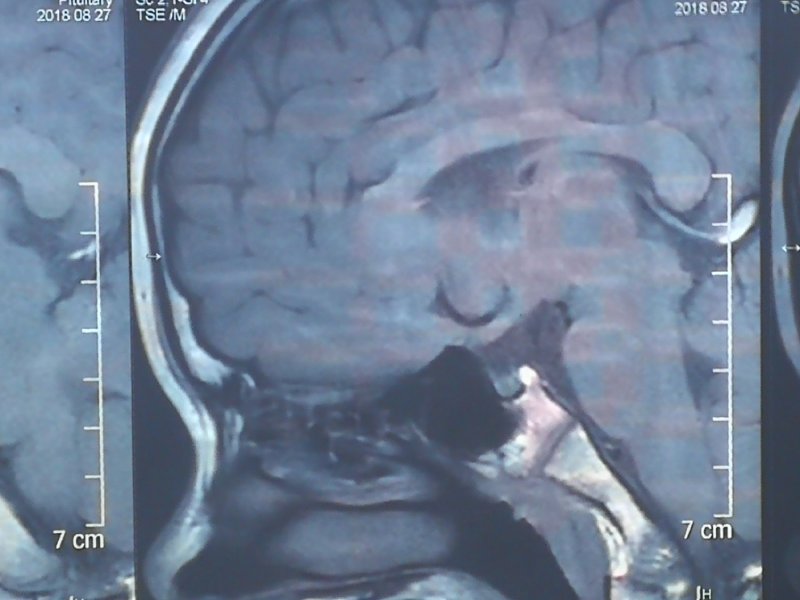

路院长详细询问病史了解到患者除了生长缓慢外没有低血糖和多尿情况,嗅觉正常。体检发现,外生殖器发育相当于3岁男孩,甲状腺正常。生长曲线显示身高小于第3百分位。化验结果提示雄激素、IGF-1和IGF-BP3很低,骨密度显示“Z= - 4.6(骨量丢失严重)”,骨龄片提示“骨龄13.8岁”,3.0T垂体增强核磁共振提示“神经垂体异位于漏斗部,垂体柄显示不清,请结合临床”。路院长凭借丰富临床经验初步判断异位神经垂体阻断垂体柄可能是病因,遂以:“垂体柄阻断综合征?低促性性腺功能减退症、垂体性矮小症”收入院行内分泌功能试验进一步明确诊断。